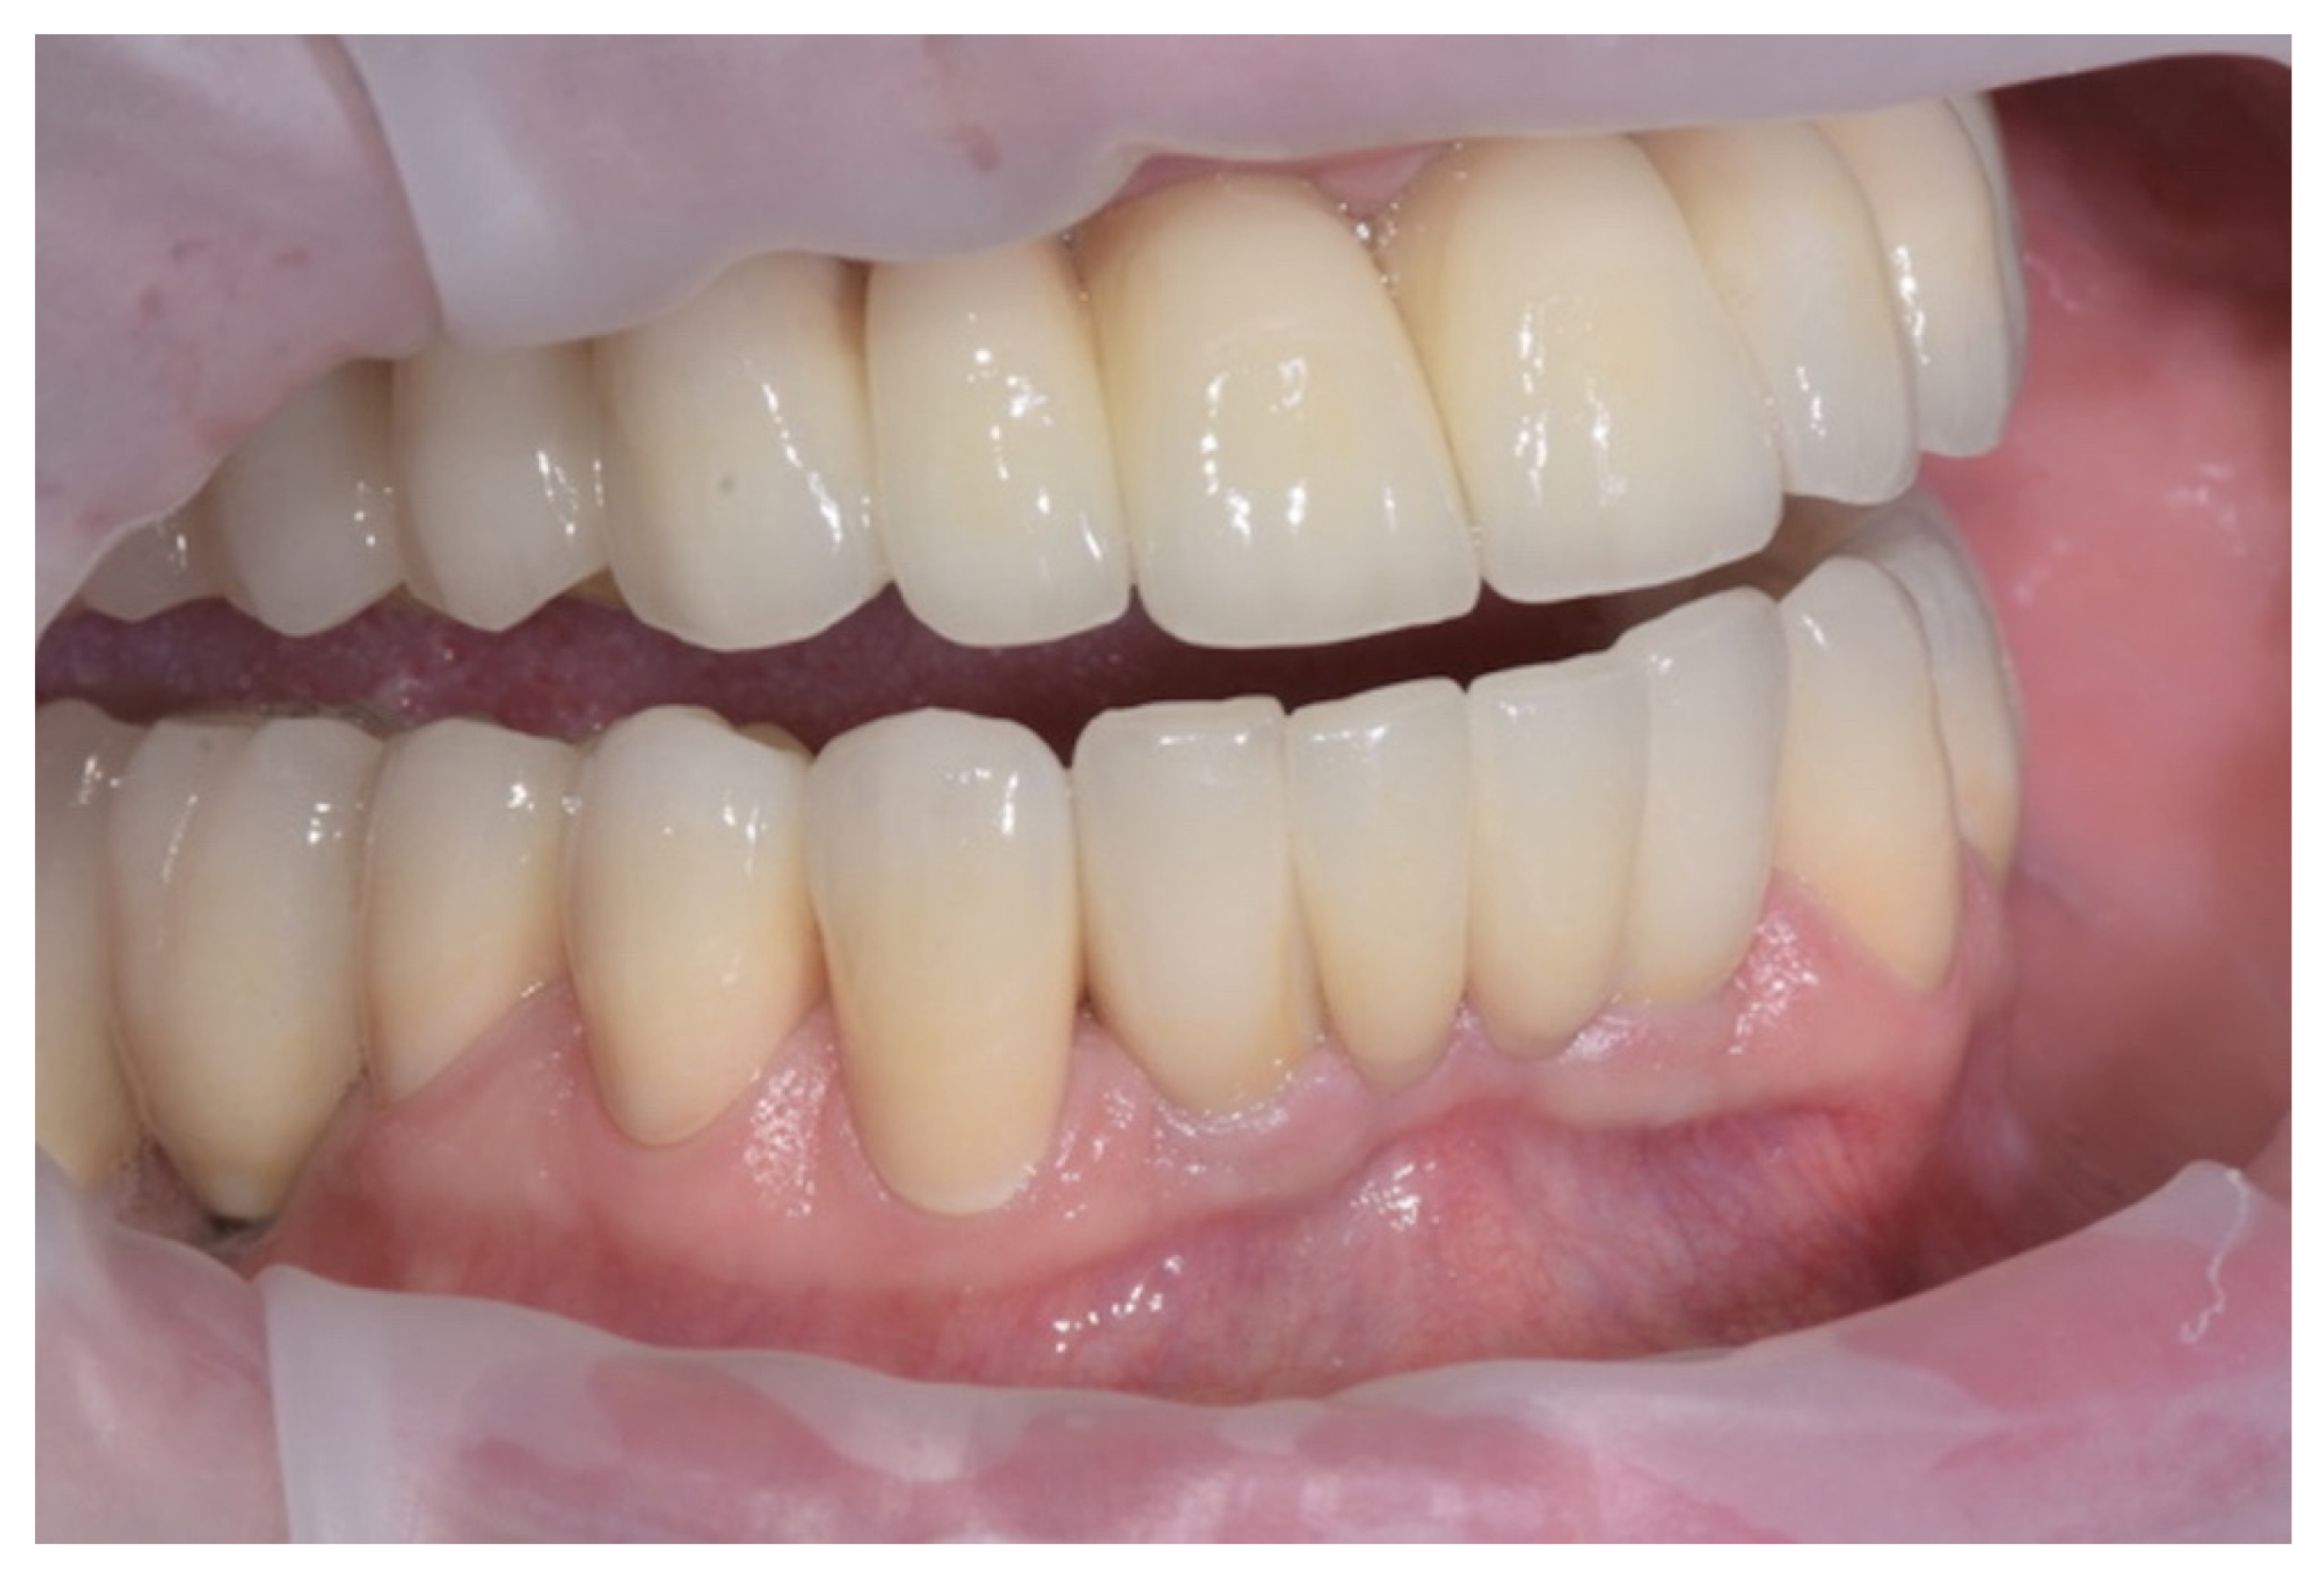

The crowns obtained were judged for clinical fit by a clinician (Figure 17). The rate of compression of sulcular tissues was good. A radiographic control taken after luting showed a proper fit (Figure 18).

Figure 17.

Crowns cemented.